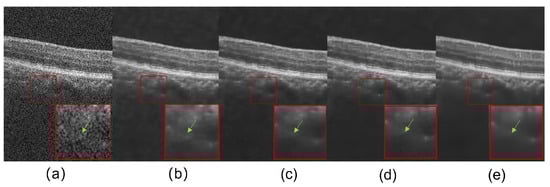

3.4. Ablation Experiments